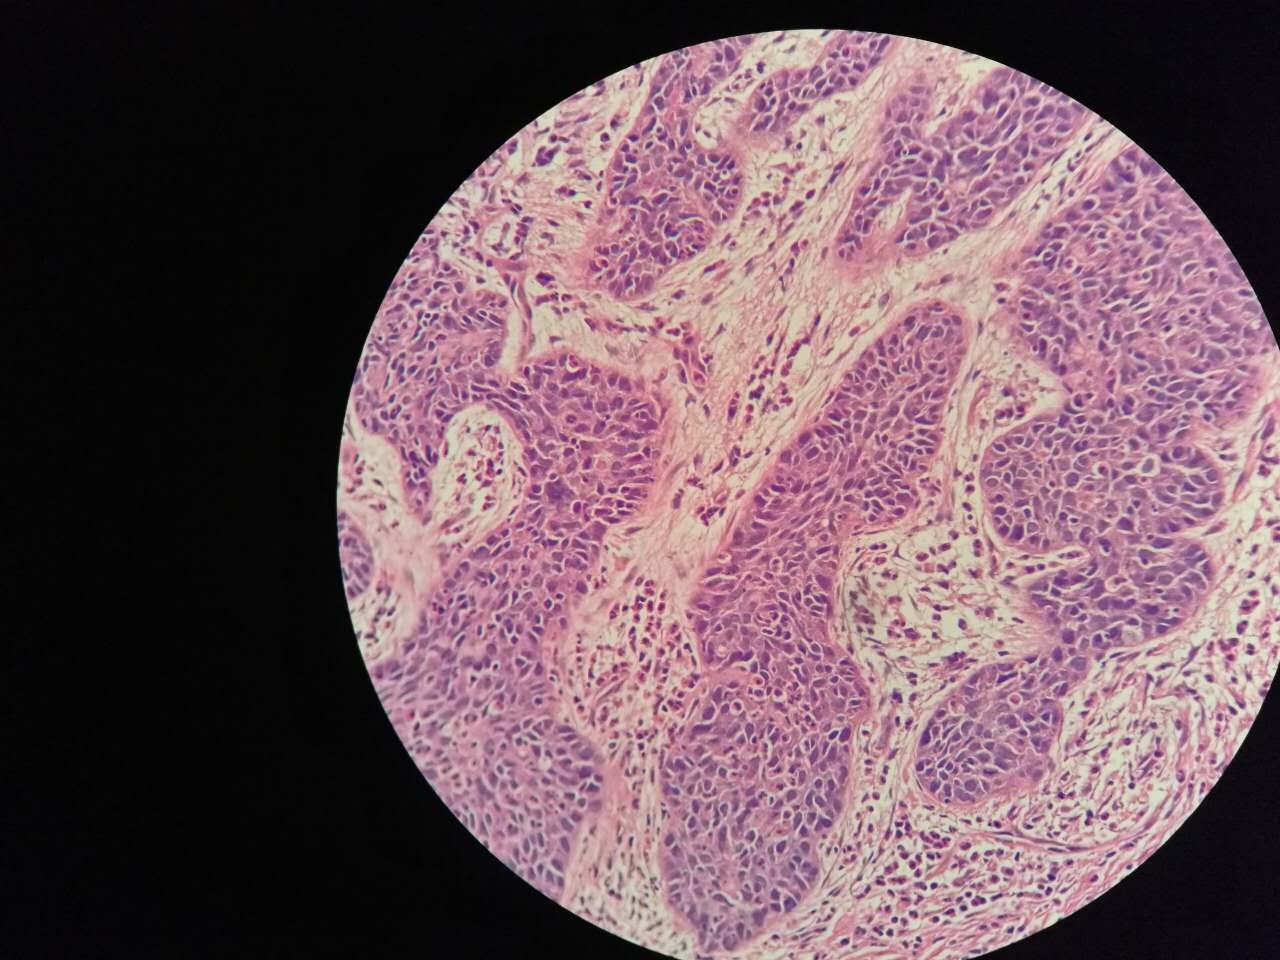

粘液型腺癌的肿瘤细胞排列整齐,核位于基底,细胞呈柱状。

肺泡间隔(间质)经常比较细

差不多都长这样

这个生长密集,相对要重

这个细支气管,一半癌浸润

肿瘤细胞形态仍然相似

中央有个肺血管,说明破坏力不强

也会有些坏死,连同粘液咳出去,就形成实变区内的空洞